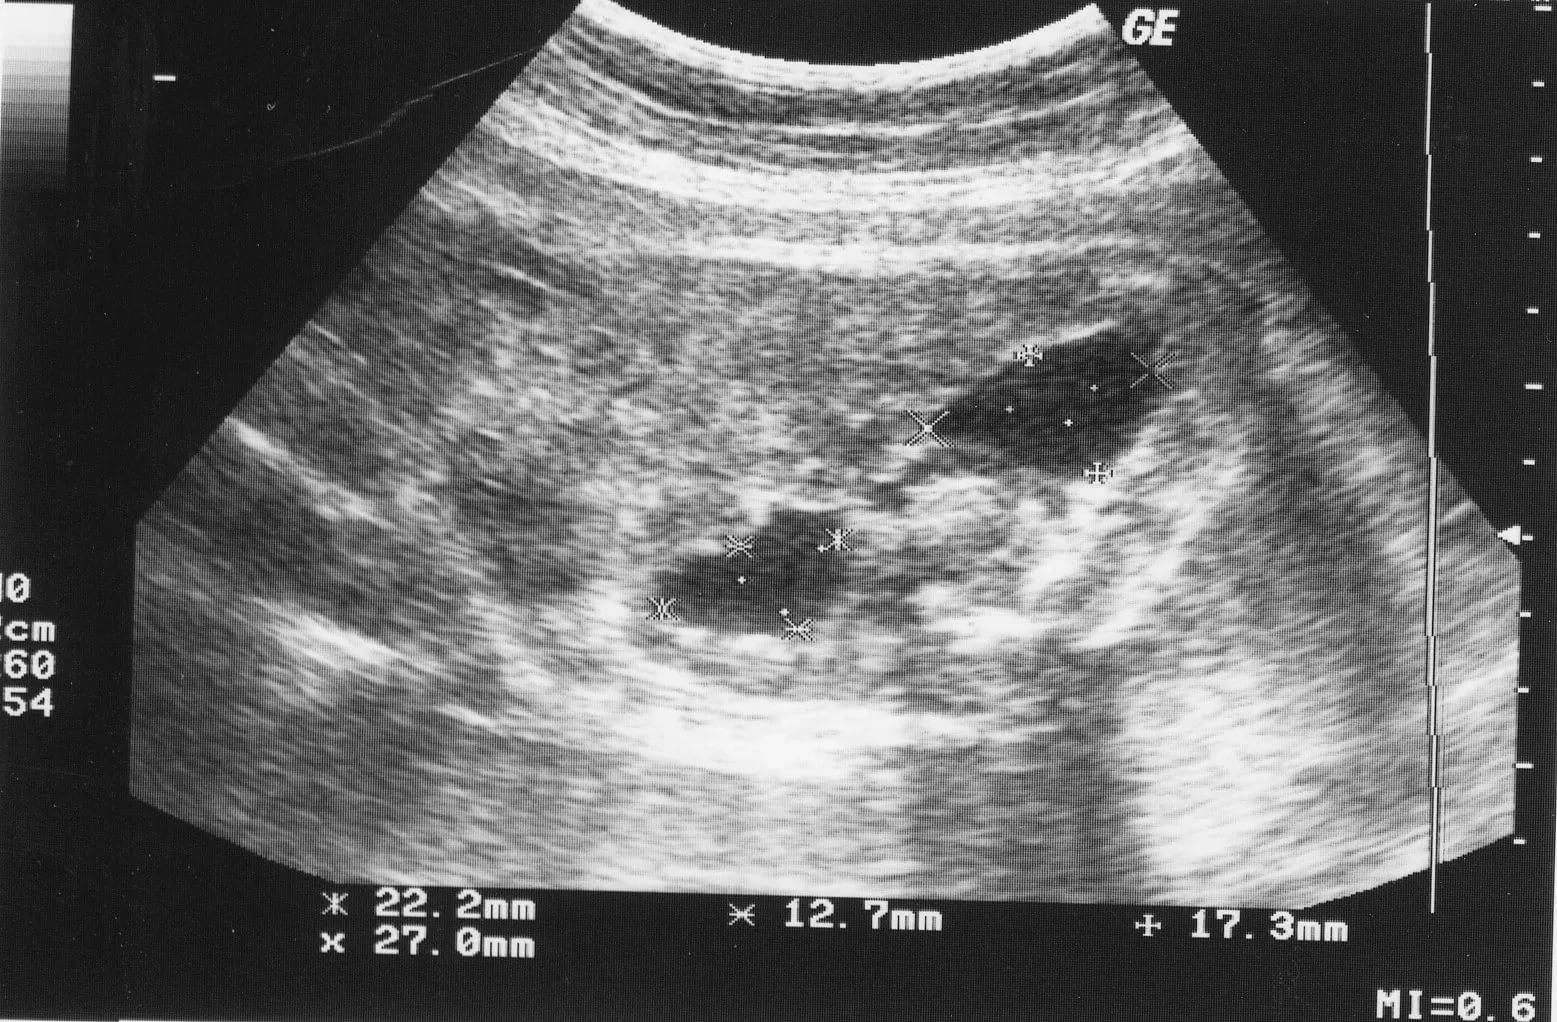

Пиелоэктазия почек у грудничка, как правило, является врожденной и бывает связана с нарушениями процессов развития организма. В этом варианте заболевание плода определяется еще в момент вынашивания, когда беременная женщина проходит плановое УЗИ на 16-20 неделе своей беременности.

Новорожденному у которого обнаружены симптомы пиелоэктазии, необходимо регулярно проходить УЗИ. На первом году жизни УЗИ проводится каждые 3 месяца, в последующие годы — 1 раз в каждые полгода.

Увеличение лоханок младенца наблюдается на протяжении беременности. Особенностью патологии является сложность постановки диагноза ввиду отсутствия норм и показателей для сравнения. Поэтому расширение лоханок почек у плода определяется, если их размер больше 4 мм на сроке 32 недели и 7—8 мм в 36 недель и на поздних сроках. Если же врач увидит цифру 10 мм, то скажет, что это выраженная пиелоэктазия левой, правой или обеих почек. Нарушение этого типа требует лечения после рождения.

Пиелоэктазия у плода, при помощи современной медицины, диагностируют еще на начальных стадиях формирования органов мочевыделительной системы. Во втором триместре, когда проводят скрининговые исследования, назначается процедура ультразвукового обследования на предмет патологий развития плода.

Конечно, поставить диагноз пиелоэктазия у плода, можно не только на основании УЗИ, так как организм ребенка постоянно изменяется, поэтому принято считать заболеванием лишь превышение увеличения почечной лоханки до 10 мм, при норме 8 мм (было установлено на сроке в 32 недели). При проведении медицинской статистики было обнаружено, что девочки болеют почти на треть меньше чем мальчики. Основной причиной возникновения такой патологии считаю заболевания почек у мамы и генетическая наследственность.

Форма тяжести и осложнения

Тяжесть пиелоэктазии почки у плода зависит от причины возникновения заболевания и степени запущенности патологического процесса. Основным оценочным критерием, по которому определяется форма тяжести пиелоэктазии, является размер переднезаднего сечения почечных лоханок. Их нормальный размер во втором триместре беременности не должен превышать 5 мм, в третьем — 7 мм. Размер лоханочных полостей более 10 мм свидетельствует о нефрозе, который может вызвать отклонения в развитии почечной паренхимы.